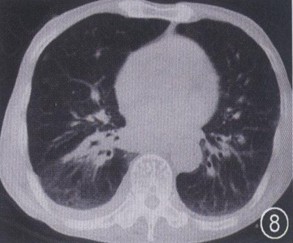

胸腔积液ct图片

胸腔积液ct表现图片

胸腔积液ct图片讲解

胸腔积液ct图片怎么看

胸腔积液ct